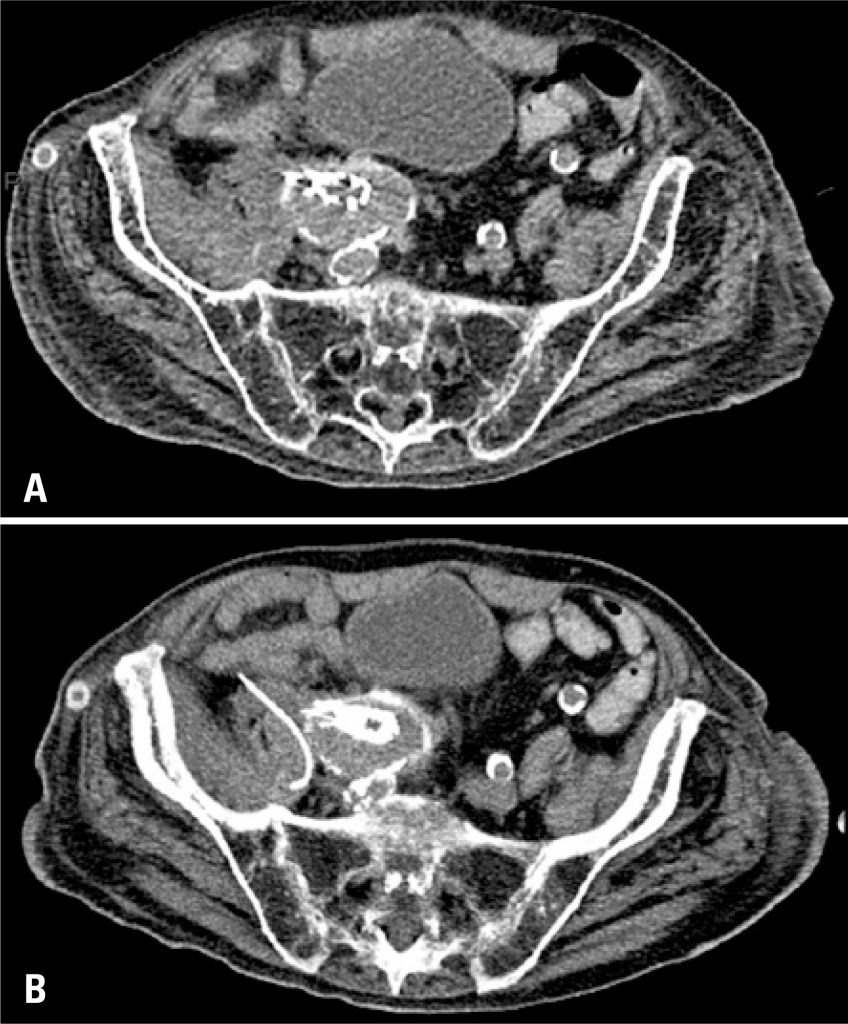

O reparo endovascular de aneurisma é uma técnica para tratamento de diversos aneurismas infrarrenais da aorta. A infecção é uma das complicações mais sérias desse tratamento, e a abordagem percutânea tem sido adotada para coleções intra-abdominais, mas seu uso para tratamento de coleções protéticas vasculares não está bem estabelecido. Descreve-se, neste trabalho, pequena série de três pacientes tratados com drenagem percutânea, que apresentaram boa resposta clínica e de imagem. A drenagem percutânea mostrou-se abordagem segura, efetiva e minimamente invasiva para tratamento desta complicação, que é potencialmente fatal.